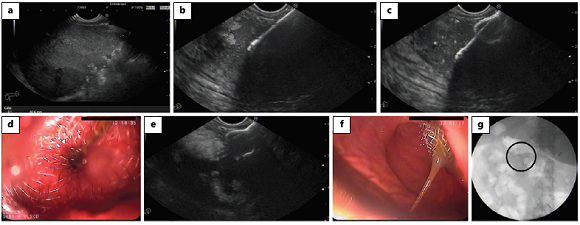

Another technique for the management of necrotic tissue consists of its mechanical removal from the collection cavity; it is named endoscopic necrosectomy. It can be performed by removal of necrotic debris using accessories or devices introduced from the digestive lumen into the collection (transluminal endoscopic necrosectomy) or by insertion of the endoscope into the cavity to remove the necrotic debris (direct endoscopic necrosectomy) [9] (Fig. 5).

Fig. 5: Direct endoscopic necrosectomy. A nasocystic catheter, placed through the stent (lumen-apposing metal stent) inside the cavity, is removed (a, b). Using forceps (c), a polypectomy snare (d) and a net (e), necrotic debris is removed to the stomach (f). Progressive resolution of the walled-off necrosis is seen with necrosectomy (g, h), showing pink granulation tissue on the cavity wall (i).

The location of drainage is important if necrosectomy is foreseen, because a too proximal (fundus, cardia) or a too distal (antrum) access may compromise the direct introduction of the endoscope into the cavity and render its manipulation more difficult [9]. Concerning stent choice, as previously mentioned, LAMS carry some theoretical advantages over other stents: (1) a larger diameter enabling passage of an endoscope through the stent for direct endoscopic necrosectomy, (2) avoidance of multiple stents or repeated balloon dilations and (3) wider flanges that provide stable apposition [1, 11]. However, prospective studies are needed to confirm the effective superiority of LAMS.

There is no consensus regarding the optimal timing for direct endoscopic necrosectomy. It is typically delayed a few days after stent placement, in order to allow maturation of the fistulous tract and decrease the risk of dislodgement, and also because some WON can resolve with stent drainage alone [45]. Nevertheless, a retrospective multicentre study [46] compared immediate (same session as stent placement) and delayed (1 week after stent placement) direct necrosectomy using LAMS and showed no significant difference in clinical success rates between the two groups. Overall adverse events were similar, though stent dislodgements were more frequent in the immediate-necrosectomy group (4.3 vs. 0%; p = 0.016) and all occurred at the index endoscopy during necrosectomy; the stent was successfully repositioned with grasping forceps in all patients without complications.

Data comparing the types of endoscope used for endoscopic necrosectomy are lacking. The ESGE suggests the use of a therapeutic gastroscope due to its larger working channel that may facilitate evacuation of fluids and entry of equipment to be used for necrosectomy [9].

No specifically designed accessories or devices are available for necrosectomy. It is performed by a combination of irrigation, sucking debris through the working channel and removing necrotic material with a removal device (such as polypectomy snares, nets, tripod retrieval forceps, grasping/rat-tooth/pelican forceps, Dormia or other stone removal baskets, or EndoRotor devices) [9, 47]. There are no studies comparing the efficacy or safety of these accessories. Snares and baskets might be preferred for the primary attempt as they are safe and quite effective [9]. The EndoRotor (Interscope Medical, Whitinsville, MA, USA), a novel automated non-thermal mechanical system designed for polyp resection in the gastrointestinal tract, is also being studied in the setting of necrosectomy and allows the necrotic tissue to be sucked into a catheter using negative pressure, cut by a rotating blade and removed to a vacuum container [47]. The ESGE suggests restraint regarding the use of high-flow water jet systems, hydrogen peroxide or vacuum-assisted closure systems [9].